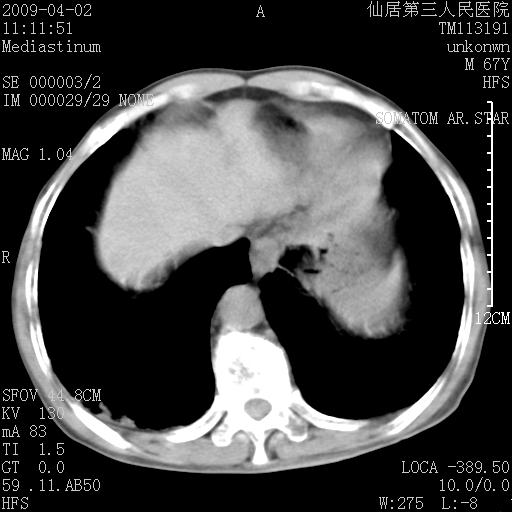

患者老年男性,乏力畏寒来诊,摄胸片示右下肺感染性病变,抗炎两周后复查胸片,无好转有进展。

后做ct平扫表现如下:

考虑右肺炎症可能性大,不除外细支气管肺泡癌

是否还要考虑肺间质纤维化,建议hrct扫描。

考虑间质性肺炎。

病灶呈蜂窝征,纵隔多个淋巴结肿大;肺泡癌需考虑

我认为普通的感染应该可以除外,间质性肺炎可能性较大,但如何解释纵膈的淋巴结肿大呢

考虑双肺间质性改变(间质纤维化?)伴右肺下叶感染。